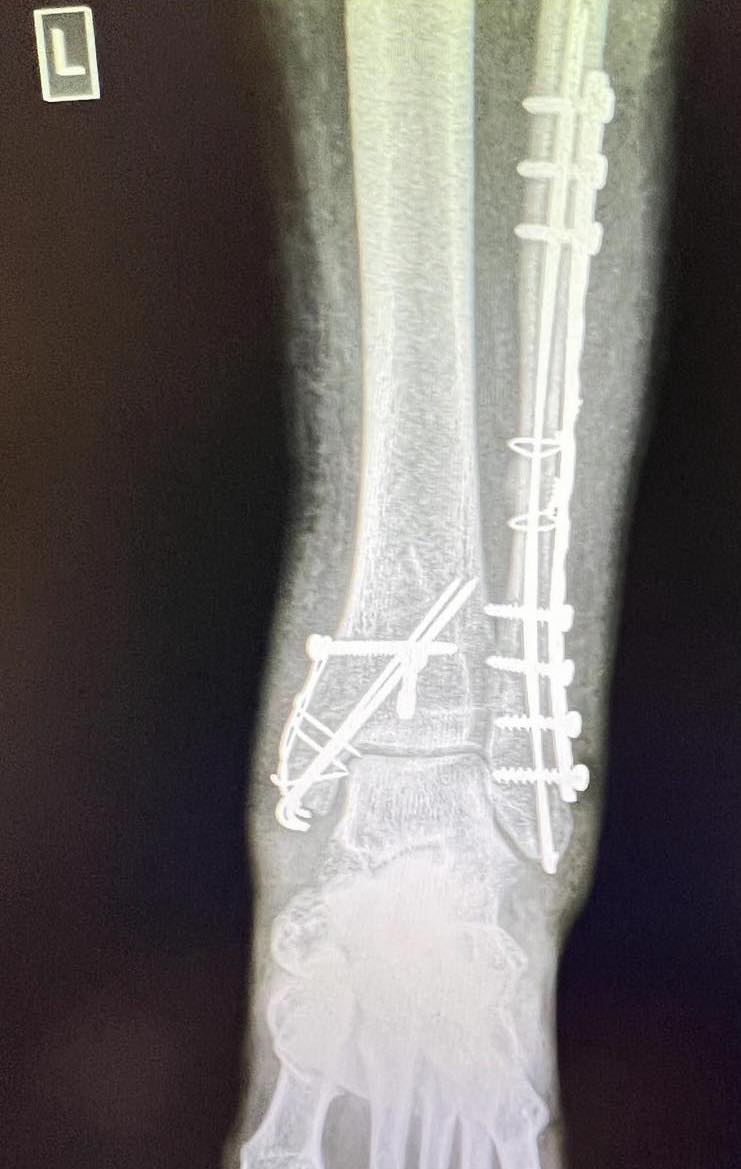

Дни преди Божана да замине за романтичния Париж, отива на купон на Българското Черноморие с приятели. „Отидохме на едно парти, което беше на едно дере. Бях пияна и дрогирана и през това време съм си пукнала крака, но съм продължила да вървя и танцувам с часове. 4 часа не съм разбрала, че съм със счупен крак. До момента, в който не припаднах от болка, кракът вече ми беше счупен на 9 места, буквално всяка кост в него беше счупена“, разкрива звездата в подкаста на Ивайло Герасимов. На брюнетката й се случило и възможно най-лошото нещо, което било възможно в ситуацията. „Виличката на хрущяла беше тотално отчупена. Просто съм стъпила накриво и съм продължила да вървя, без да усетя нищо, трябваше веднага да вляза в болница, защото положението беше много опасно“, допълва самата тя.

Кацарова обяснява, че освен почивката си до Париж е провалила цялото си лято. Колоритната готвачка е носила 2 месеца гипса на крака си, а след това бавно е възстановила и разходките. „120 грама желязо имам в крака. След като се възстанових, обиколих няколко места - Ню Йорк, Берлин, Грузия, Истанбул, Амстердам и Барселона, за щастие не пищя на проверката на летището“, казва с усмивка тя.